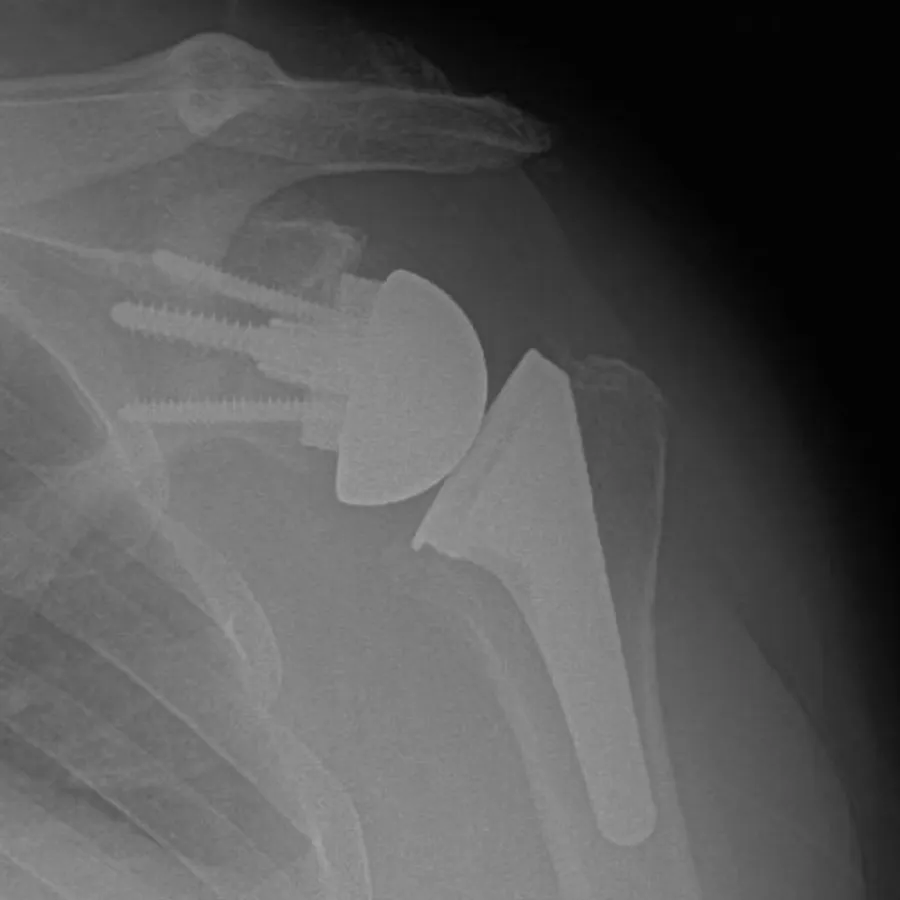

X-ray showing shoulder joint replacement with metal prosthesis and screws in humerus bone.

Reverse Shoulder Replacement:

This innovative technique is primarily used for patients with a torn rotator cuff and severe arthritis, fractures, irreparable chronic rotator cuff tears or those who have had previous unsuccessful shoulder replacement surgeries (revision shoulder replacement). Some patients who have normal rotator cuffs with severe arthritis can benefit from a reverse shoulder replacement if they are older or have worn away too much bone on the socket. In reverse shoulder replacement, the normal ball-and-socket structure is reversed; the ball component is attached to the shoulder blade, and the socket is placed at the top of the humerus. This arrangement allows the deltoid muscle to power the arm, compensating for the damaged rotator cuff or alterations in anatomy.